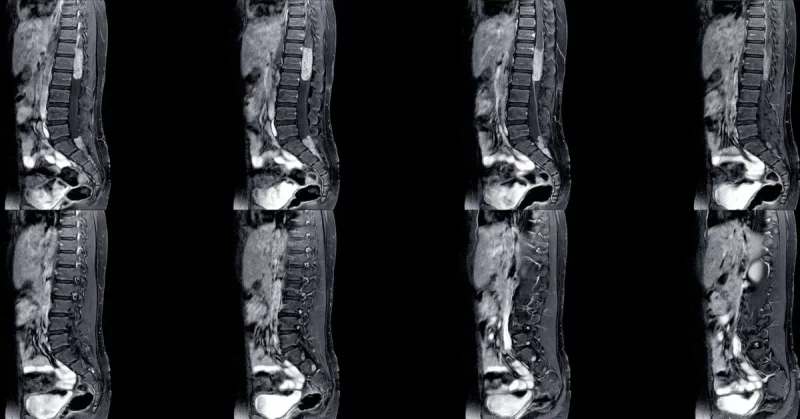

Imaging Studies

Magnetic resonance imaging, or MRI, is the gold standard for diagnosing conus medullaris syndrome. An MRI provides detailed images of the spinal cord and surrounding structures, helping identify compression, inflammation, or injury.

In some cases, computed tomography (CT) scans may be used, especially when trauma is involved.